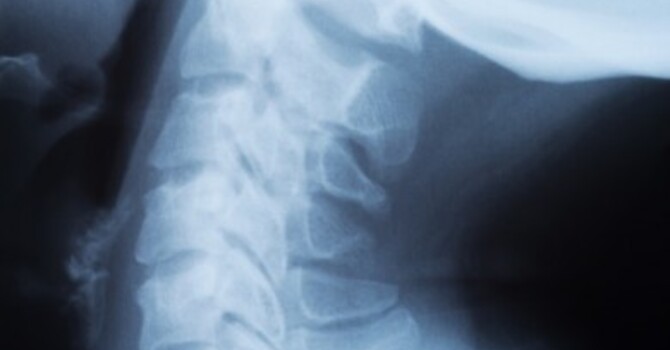

Chiropractors employ manual manipulation of the spine including other alternative forms of treatment such as massages and individualized diet. The idea is to align the spine to ensure the body’s innate ability to heal even without the application of medication or surgical procedures. With manipulation, it is possible for the joints to restore their mobility because the injury caused to these parts of the body has been addressed.